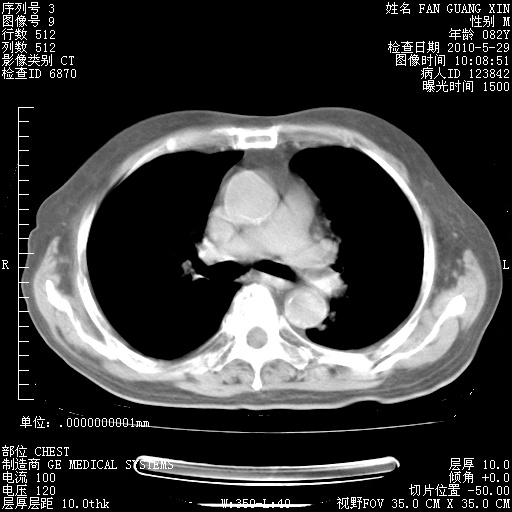

再治疗10天后的肺部CT 纵膈窗